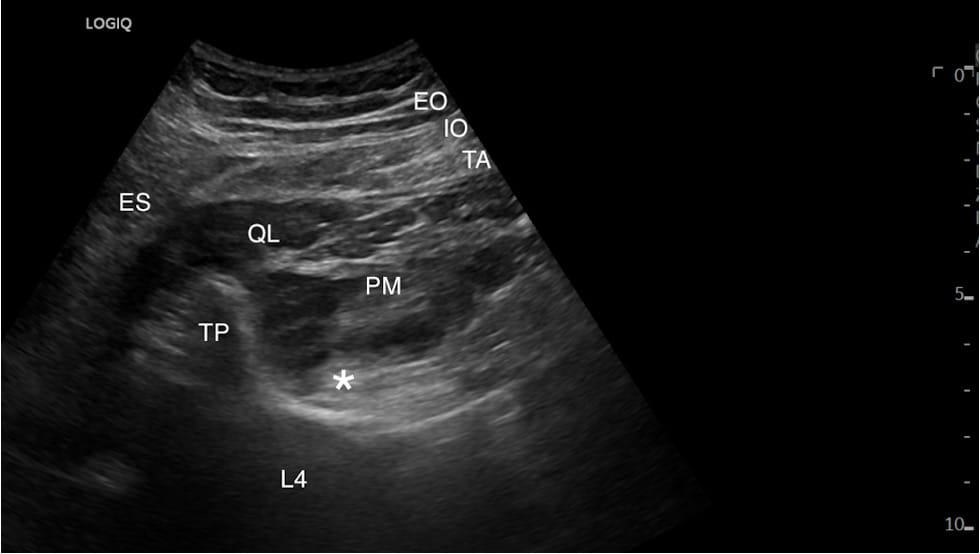

At this point, we aim to optimize a view of the “shamrock sign.” The leaves of the shamrock include the psoas muscle (anteriorly), QL (laterally), and erector spinae muscles (posteriorly), with the transverse process resembling the stem of the shamrock (Figure 2).11 Color Doppler is used to identify the lumbar arteries and plan for a safe needle trajectory (Figure 3).

ES = erector spinae muscles, QL = quadratus lumborum muscle, PM = psoas major muscle, TP = transverse process, L4 = lumbar 4 vertebral body, * = lumbar plexus, EO = external oblique muscle, IO = internal oblique muscle, TA = transversus abdominis muscle